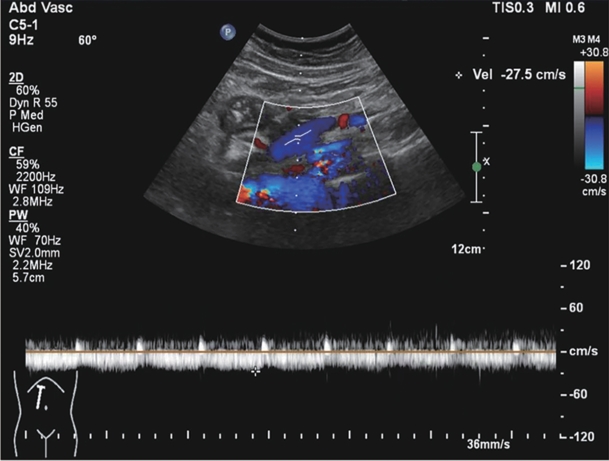

失代偿期乙型/丙型肝炎肝硬化患者合并门静脉血栓的列线图模型建立与验证

田仁海, 王远珍, 魏红艳, 常丽仙, 刘春云, 刘立

2025, 41(8): 1579-1588. DOI: 10.12449/JCH250817

摘要(424) HTML (177) PDF (2198KB)(60)

摘要:

目的  分析失代偿期乙型/丙型肝炎相关肝硬化患者合并门静脉血栓(PVT)的独立影响因素,建立列线图风险预测模型并进行验证。  方法  回顾性收集2022年1月—2023年12月首次在昆明市第三人民医院就诊的1 116例失代偿期乙型/丙型肝炎肝硬化患者的临床资料,并按是否合并PVT分为PVT组和对照组。计量资料两组间比较采用成组t检验或Mann-Whitney U检验。计数资料两组间比较采用χ2检验。用单因素分析、最小绝对收缩和选择算子(Lasso)回归筛选变量,多因素二元Logistics回归分析筛选独立影响因素并建立预测模型,列线图可视化模型;并使用受试者操作特征曲线(ROC曲线)下面积(AUC)、Hosmer-Lemeshow检验、Bootstrap法自抽样1 000次、校准曲线、临床决策曲线、临床影响曲线验证模型。  结果  PVT组178例,对照组938例,合并PVT患病率15.9%(178/1 116)。男性占68.5%(764/1 116)、饮酒者占51.0%(569/1 116)、Child-Pugh B级者78.8%(879/1 116)、有腹水者67.1%(749/1 116)。PVT组与对照组比较,年龄(Z=-2.362)、凝血酶原时间(Z=-2.403)、国际标准化比值(Z=-2.470)、游离甲状腺素(Z=-5.910)、D-二聚体(Z=-5.764)、IL-6(Z=-6.581)、IL-10(Z=-3.915)、IL-8(Z=-3.705)、门静脉内径(Z=-9.690)、脾厚径(Z=-7.183)升高,而白细胞(Z=-2.115)、血小板(Z=-3.026)、纤维蛋白原(Z=-2.169)、谷氨酸氨基转移酶(Z=-3.151)、前白蛋白(Z=-3.509)、胆碱酯酶(Z=-3.415)、甲胎蛋白(Z=-3.513)、甘油三酯(Z=-2.679)、CD3+Z=-6.059)、CD4+Z=-7.257)、CD8+Z=-2.340)、CD4+/CD8+Z=-4.479)、三碘甲状腺原氨酸(Z=-3.338)、游离三碘甲状腺原氨酸(FT3)(Z=-9.560)、门静脉血液流速(Z=-4.568)降低,差异均有统计学意义(P值均<0.05)。经Lasso回归筛选出有意义的变量再进行多因素Logistics回归分析,显示年龄(OR=1.046,95%CI:1.026~1.066)、CD4+/CD8+OR=0.568,95%CI:0.410~0.787)、FT3(OR=0.956,95%CI:0.944~0.968)、IL-10(OR=1.021,95%CI:1.001~1.042)、门静脉内径(OR=1.446,95%CI:1.329~1.574)、脾厚径(OR=1.035,95%CI:1.014~1.055)为合并PVT的独立影响因素,建立模型Logit(P)=-8.784+0.045×年龄-0.566×CD4+/CD8+-0.046×FT3+0.021×IL-10+0.369×门静脉内径+0.034×脾厚径,建立并验证列线图模型,AUC=0.859(95%CI:0.833~0.887)。Hosmer-Lemeshow检验显示,模型拟合较好(χ2=11.349,P=0.183)。Bootstrap内部验证,平均绝对误差=0.006,C指数=0.855。决策曲线显示,在较宽范围内,临床净获益高。  结论  年龄,CD4+/CD8+、FT3、IL-10、门静脉内径、脾厚径可能是失代偿期乙型/丙型肝炎肝硬化患者合并PVT的独立影响因素。以此6个变量建立并验证的预测模型,可能有助于临床上早期预测失代偿期乙型/丙型肝炎肝硬化患者合并PVT的风险。